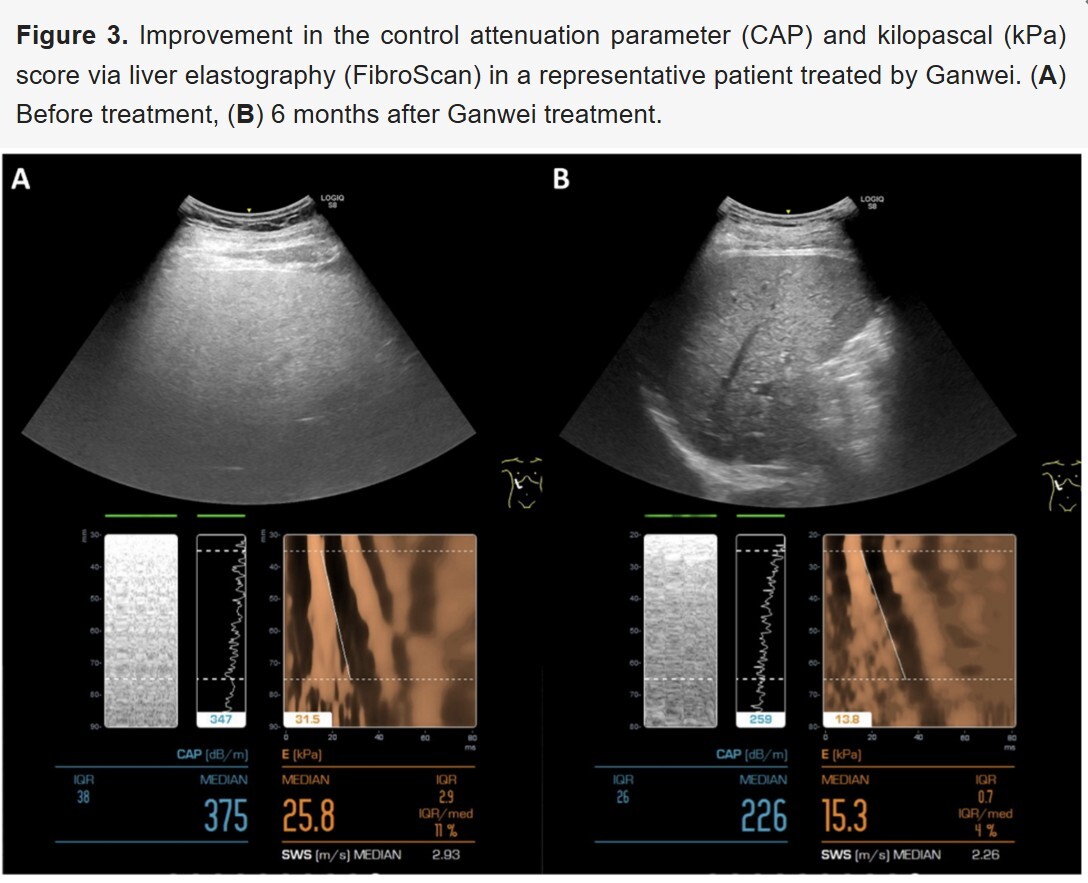

澤生研發團隊最新實驗成果現已發布。

本次研究數據展現了具有意義的重大突破。